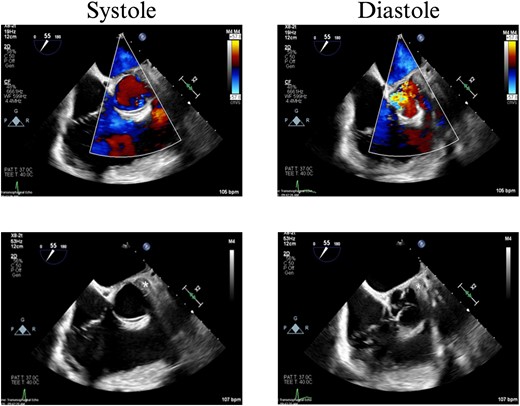

On hospital Day 7, the patient had acute hypoxic respiratory failure. CT chest found a right segmental pulmonary embolism and a retained bullet near the aortic root. A TEE was repeated, this time demonstrating severe aortic insufficiency (Fig. 4), and a bullet in the left coronary cusp. Cardiothoracic surgery was consulted for evaluation and management. The next day, the patient went to the OR for median sternotomy, cardiopulmonary bypass, aortic root repair with patch, re-attachment of the left coronary cusp, and removal of the bullet from the aortic root.

TEE with intracardiac bullet, severe aortic insufficiency. The bullet is labeled by an asterisk, with shadow artifact posterior to the bullet.

Case 2 involved a hemodynamically unstable patient with multiple thoracoabdominal GSWs. The surgical team identified six GSWs and five retained bullets. The patient’s instability precluded CT imaging. A cardiac injury was suspected due to a bullet overlying the cardiac silhouette and significant chest tube output. Thoracotomy confirmed a cardiac injury with tamponade, necessitating immediate repair. The bullet trajectory suggested it passed through the heart and diaphragm into the abdomen. TEE revealed no intracardiac shunting, valve insufficiency, or bullet. The bullet injured the left ventricle and embolized to the aortic root, becoming symptomatic on hospital Day 7. A CT scan suggested an intravascular bullet near the aortic valve, confirmed by TEE showing severe aortic insufficiency. The patient required four operations for definitive management. This case underscores the risks of conservative management and the need for thorough evaluation in unstable patients.